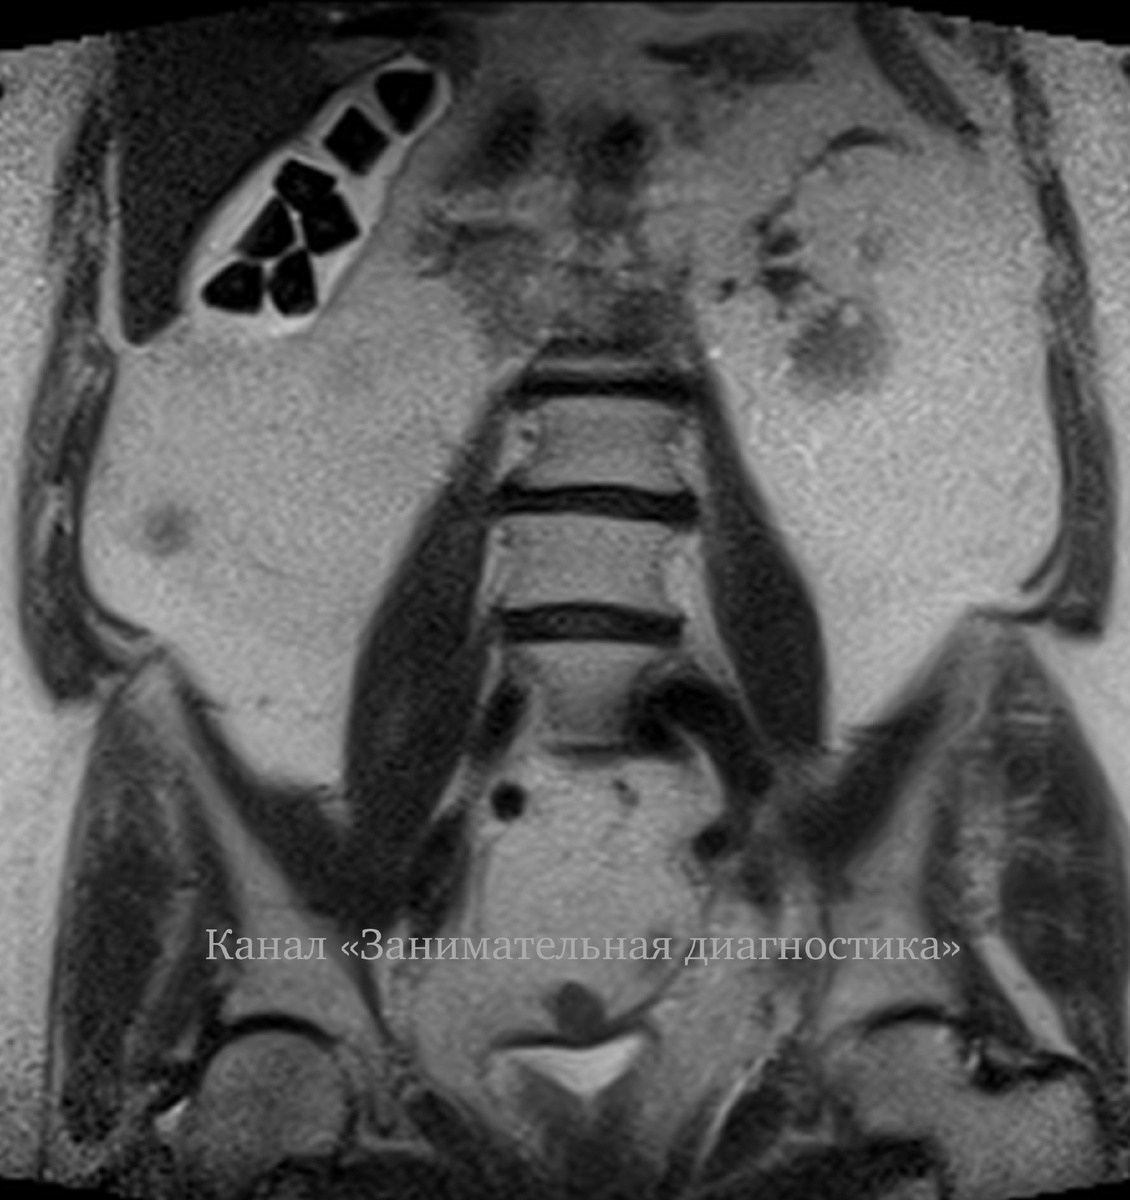

"Странные" камни в желчном пузыре

🧐 Нет, это не игральные кости в животе. И не детские кубики.

Это камни в желчном пузыре, которые мы случайно обнаружили у пациента (обследуя малый таз).

Природа, видимо, решила, что округлые формы — это скучно, и устроила геометрический бунт в животе.

Желчные камни — это не просто скучные булыжники, а настоящие минеральные скульптуры, которые организм лепит в свободное от переваривания время. И если большинство из них — гладкие и округлые, то иногда они вдруг становятся геометрическими абстракциями. Почему?

Классические холестериновые камни мягкие и обкатываются, как галька. Но если в составе преобладает билирубин или кальций, они кристаллизуются в угловатые формы.

• Билирубиновые камни — "бунтари", которые не хотят подчиняться законам округлости, растут как им вздумается, иногда образуя треугольники или многогранники.

• Кальциевые отложения — любят слои, острые грани и сложные структуры.

Если камень прилипает к стенке пузыря или застревает в протоке (или его владелец любит много спать - шутка), у него нет возможности кататься и стачиваться. Вместо этого он обрастает новыми слоями асимметрично — и вот вам квадратный или треугольный "шедевр".

Если желчь густая и застаивается, кристаллы растут медленно и хаотично, создавая угловатые формы.